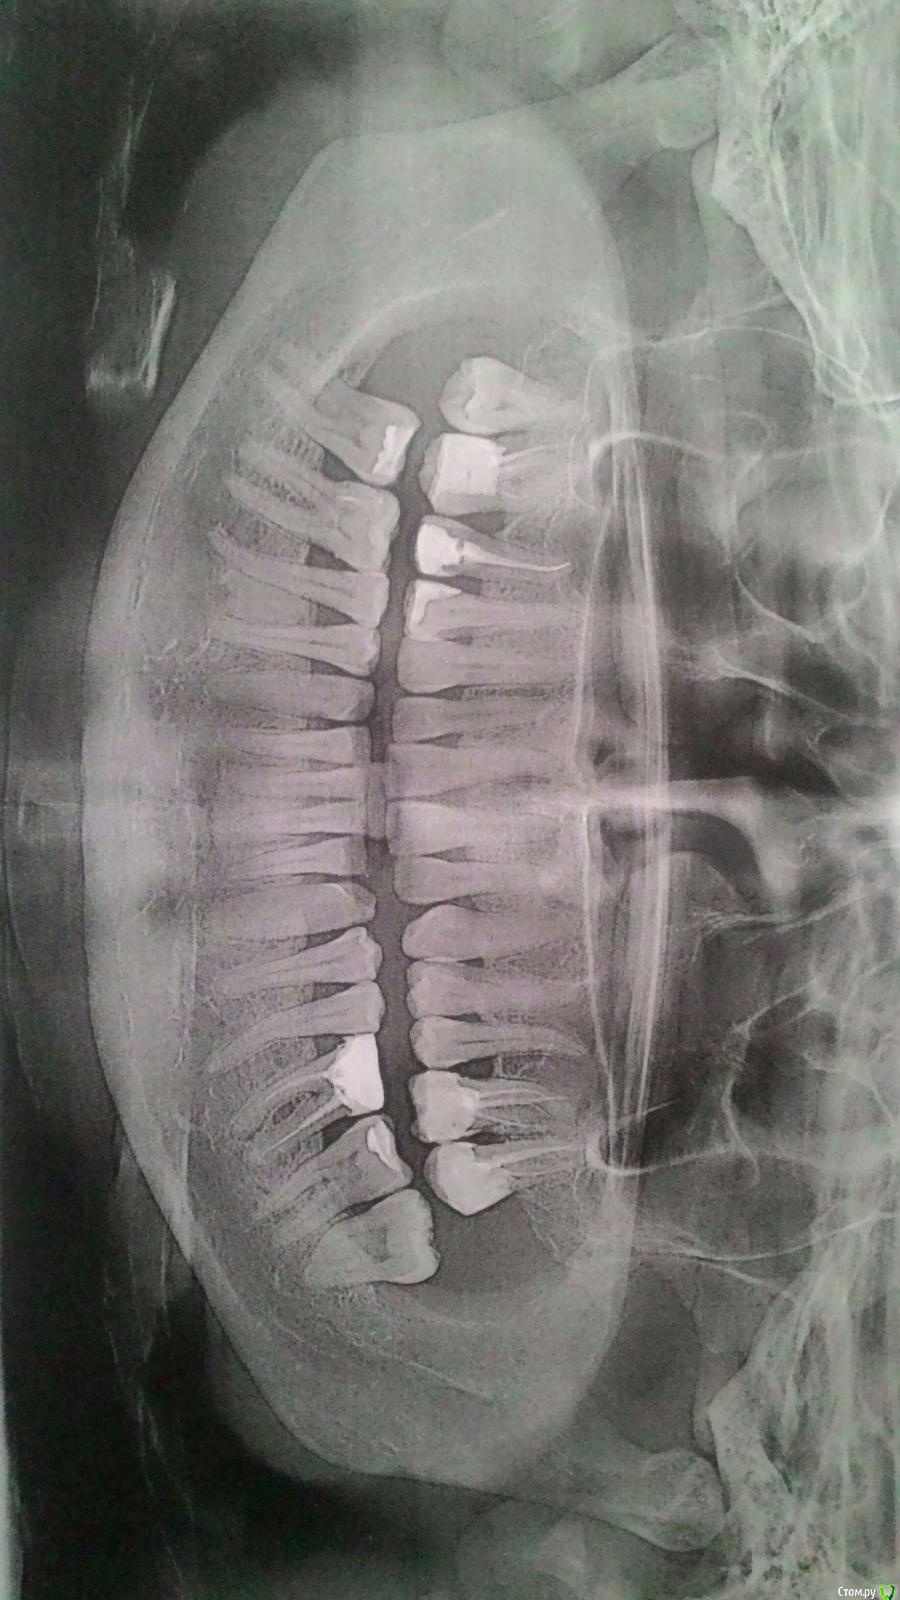

Dkat Опубликовано 26 апреля, 2018 Поделиться Опубликовано 26 апреля, 2018 Добрый день, подскажите, есть ли необходимость удалить две оставшиеся восьмерки? И как срочно нужно удалять шестерку внизу слева? (Она не беспокоит)Спасибо Ссылка на комментарий

Irouil Опубликовано 28 апреля, 2018 Поделиться Опубликовано 28 апреля, 2018 Восьмерки удалять нужно. Шестёрку - чем раньше, тем лучше. Если не хотите перелечивать. 1 Ссылка на комментарий

Dkat Опубликовано 28 апреля, 2018 Автор Поделиться Опубликовано 28 апреля, 2018 Спасибо.Шестерку перелечить хочу, но врачи, у которых я консультировалась, говорят - только удаление. Имеет смысл искать доктора, который возьмется за лечение? Ссылка на комментарий

Irouil Опубликовано 28 апреля, 2018 Поделиться Опубликовано 28 апреля, 2018 Не просто доктора, а эндодонтиста и с микроскопом. И у него уже спрашивать, имеет ли смысл перелечивать. 1 Ссылка на комментарий

Dkat Опубликовано 28 апреля, 2018 Автор Поделиться Опубликовано 28 апреля, 2018 Эндодонтисты с микроскопом как раз и не взялись. Сказали - по КТ каналы непоходимы ((( Ссылка на комментарий

Irouil Опубликовано 28 апреля, 2018 Поделиться Опубликовано 28 апреля, 2018 Эндодонтисты с микроскопом как раз и не взялись. Сказали - по КТ каналы непоходимы (((Если не найдете врача с обратным мнением, то удаляйте и протезируйте в кратчайшие сроки. 1 Ссылка на комментарий